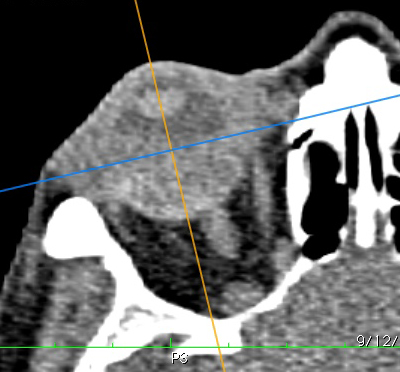

The recommended method of preparing CT and MR images for Plaque Simulator is to use the OsiriX application to create up to 5 multiplanar reconstructions from an axial 3D series of DICOM compatible image files. The spacing between slices should be as small as possible (3 mm maximum) without losing soft tissue image quality. Try to avoid using high speed protocols that result in grainy images of the soft tissues of the eye.

Poor soft tissue imaging quality. The graininess makes it difficult to differentiate between soft tissues such as the sclera, tumor, vitreous and blood vessels in the optic nerve.

This is an example of good soft tissue CT imaging quality. The sclera is distinctly visible, as is the tumor. One can even identify where the optic nerve and blood vessels penetrate the eye marking the optic disc. The apex of the cornea and the lens are distinct. This enables the yellow line in the examples to project to the posterior pole.